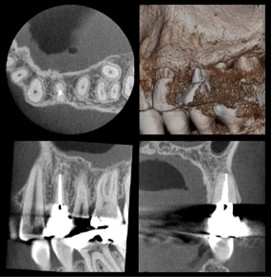

高精細な3D画像が撮影可能な『歯科用CT』

副鼻腔から歯根の形態、顎関節まで詳細に評価でき、幅広い診断・治療に対応可能です。

CT画像を活用した治療

インプラント治療

骨の厚みや密度を正確に把握し、安全な埋入計画。

親知らずの抜歯

神経や血管の位置を正確に把握し、安全な抜歯計画

歯根嚢胞や腫瘍の診断

病変の正確な位置、広がり、周囲組織との関係を把握

歯内療法の精密検査

根管の形態や病変の詳細を把握

歯根破折の診断

あらゆる角度から破折線を確認